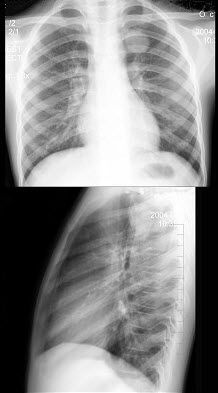

192、多项选择题

男,1岁零8个月,生长发育差,易患呼吸道感染,心悸气促,心脏正、侧位片检查如图所示,正确的描述和诊断是()

A.正位示心影向两侧扩大,心尖左移

B.肺纹理增多

C.侧位示心前间隙变窄,心后食管前三角间隙消失

D.房间隔缺损

E.室间隔缺损

193、单项选择题 最容易观察颈椎结核椎旁脓肿的体位是()